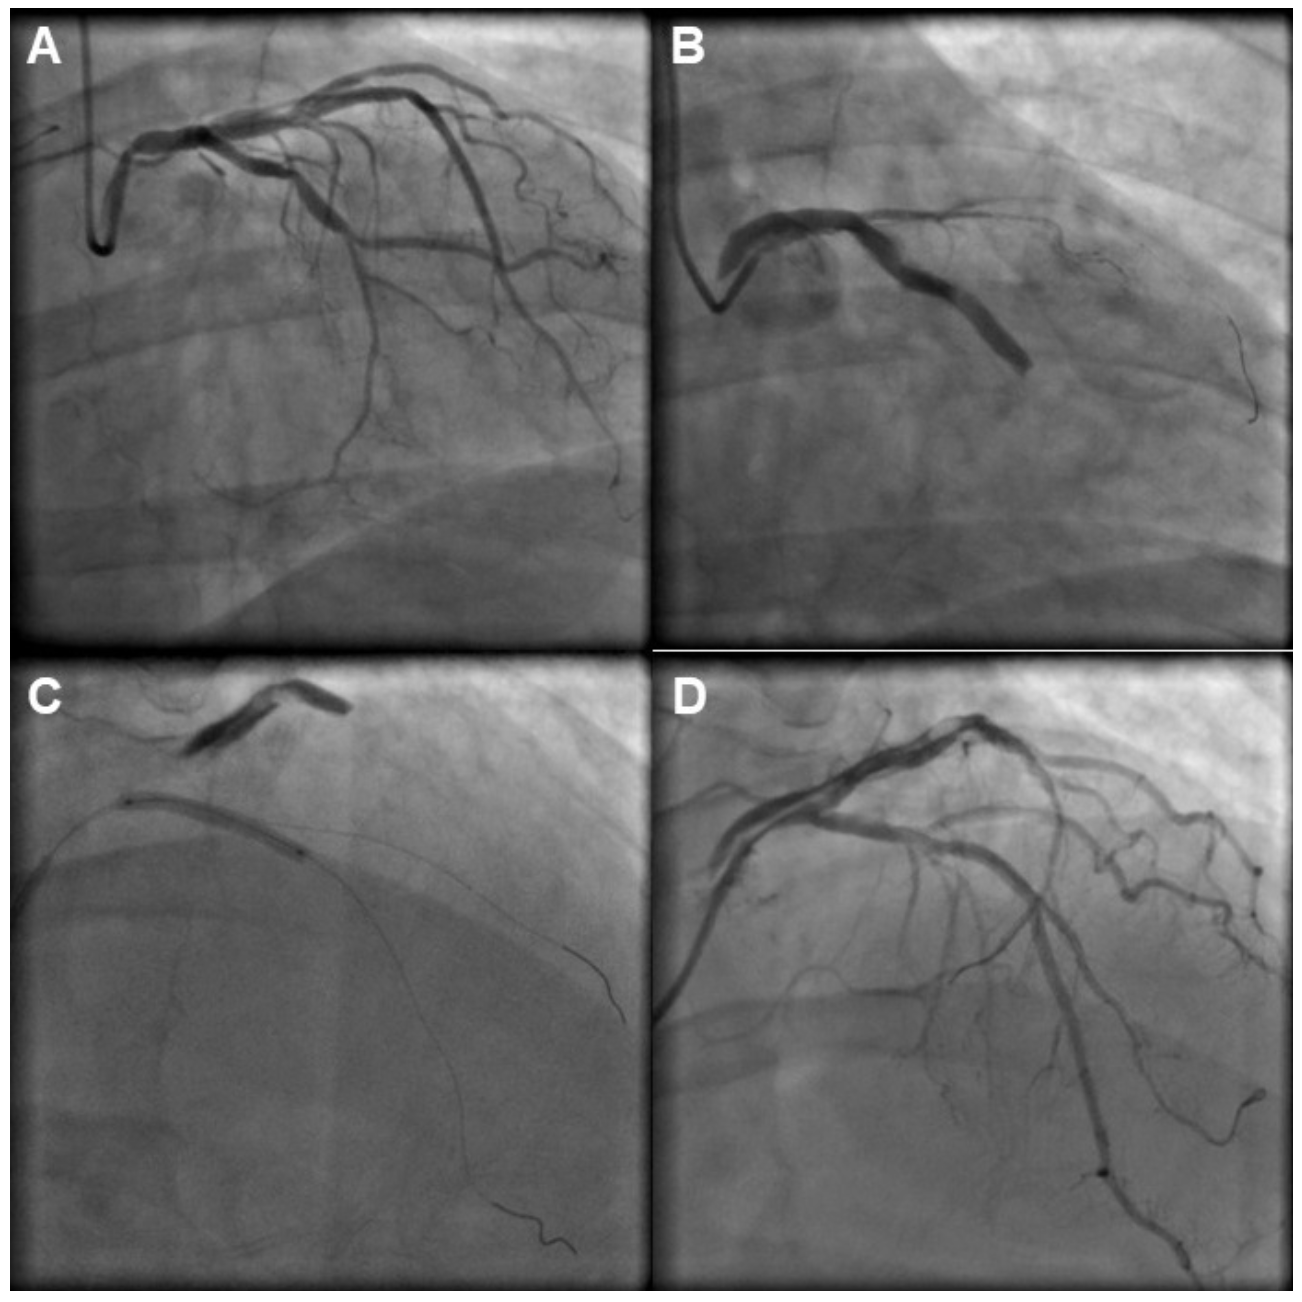

Guide-catheter dissection is seen in <1% of PCI and is associated with deep engagement of large catheters into smaller, diseased arteries.12 In our study, guide-catheter positioning caused the dissection in 18% of the dissection cases (Figures 4 and 5). Amano et al3 examined the incidence and outcomes of guide catheter-induced iatrogenic coronary artery dissection in a study of 77,257 patients and reported an incidence of 0.14%, which is similar to our rate of dissections caused by the guide catheter (0.24%). Hiraide et al10 analyzed data from 17,225 consecutive patients undergoing PCI at 15 hospitals between 2008 and 2016 and reported the incidence, predictors, and in-hospital outcomes of catheter-induced coronary artery dissection. Catheter-induced dissection occurred in 185 patients (1.1%). Similar to our study, catheter-induced dissections was associated with high in-hospital mortality (6.5%) and in-hospital adverse cardiovascular events (14.1%). Patients who experienced catheter-induced dissections with decreased residual flow were at higher risk of postprocedural complications.10